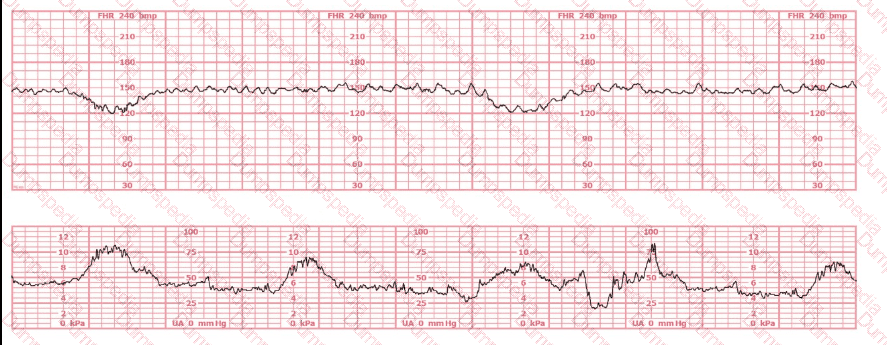

A woman at 39-weeks gestation is being induced. She has chronic hypertension controlled by methyldopa (Aldomet). Spontaneous rupture of membranes has occurred; she is 10 cm dilated and at +1 station. The fetal monitor tracing shown is obtained by spiral electrode and tocodynamometer. The next best appropriate action is to: